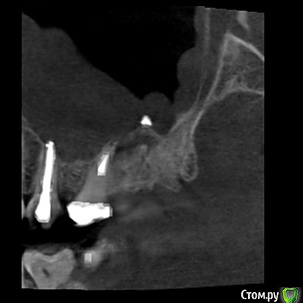

Tymchynskyi Опубликовано 2 мая, 2016 Поделиться Опубликовано 2 мая, 2016 (изменено) Пациентка обратилась по поводу периодически повторяющихся ноющих болей в области 17го зуба, постоянное ощущение дискомфорта.Месяц назад пошла на консультацию к ЛОРу где ей поставили диагноз правостороннего гайморита.Сначала баловались *кукушками* - не помогло, затем сделали прокол, и со слов пациентки, док. сказал что из пазухи исходил кариозный запах, характерный для проблемного зуба.Объективно: 16-17 зубы лечены 2г назад и покрыты МК спаянными коронками.Десневой край вокруг коронок цианотичный, нарушена БШ.В 17 зубе 3-ногая ВКВ, в 16 СВШ.Вертикальная перкуссия 17 слабо болезненная.Отправил на КТ.На буккальных апексах 16-17 и небном 17 очаги деструкции.Но больше всего интересует наличие инородного тела над апексом небного корня зуба 17(диаметр порядка 2мм).Или это артефакт??То ли обтурационный материал мигрировал вглубь пазухи, то ли ЛОР чето намудрил при вмешательстве...Что скажете?Какие прогнозы? Изменено 2 мая, 2016 пользователем Tymchynskyi Ссылка на комментарий

dantist_movani Опубликовано 2 мая, 2016 Поделиться Опубликовано 2 мая, 2016 В пазухе пломбировочный материал, опять к эндоскописту. 1.6 и 1.7 удалять. Ссылка на комментарий

DmitrySH Опубликовано 2 мая, 2016 Поделиться Опубликовано 2 мая, 2016 Пломбировочный материал в каналах на КТ сильно фонит, сложно понять что там с зубами, и сколько их осталось. Материал в пазухе проблем не должен создавать. Главное убрать источник инфекции. 3 Ссылка на комментарий